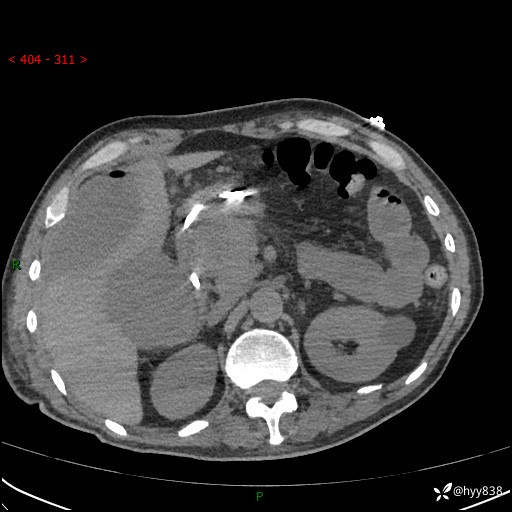

腹部CT平扫

增强